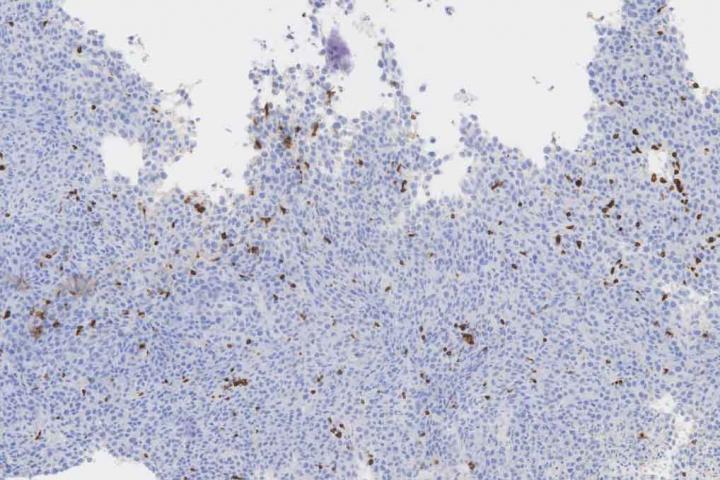

image: Immunohistochemistry staining of T cell populations in colorectal tumor tissue.

The research team used this probiotic delivery system to release nanobodies blocking PD-L1 and CTLA-4 within tumors in mouse models of lymphoma and colorectal cancer. It is already known that tumors express these checkpoints to stop the immune system, specifically T cells, from functioning properly. The goal of blocking PD-L1 and CTLA-4 is to remove the "brakes" and enable T cells to attack the cancer. A direct comparison to clinically relevant antibodies against the same target showed that their probiotic therapy was more effective, leading to complete tumor regression and prevention of metastatic formation in early and late-stage mouse models of lymphoma.